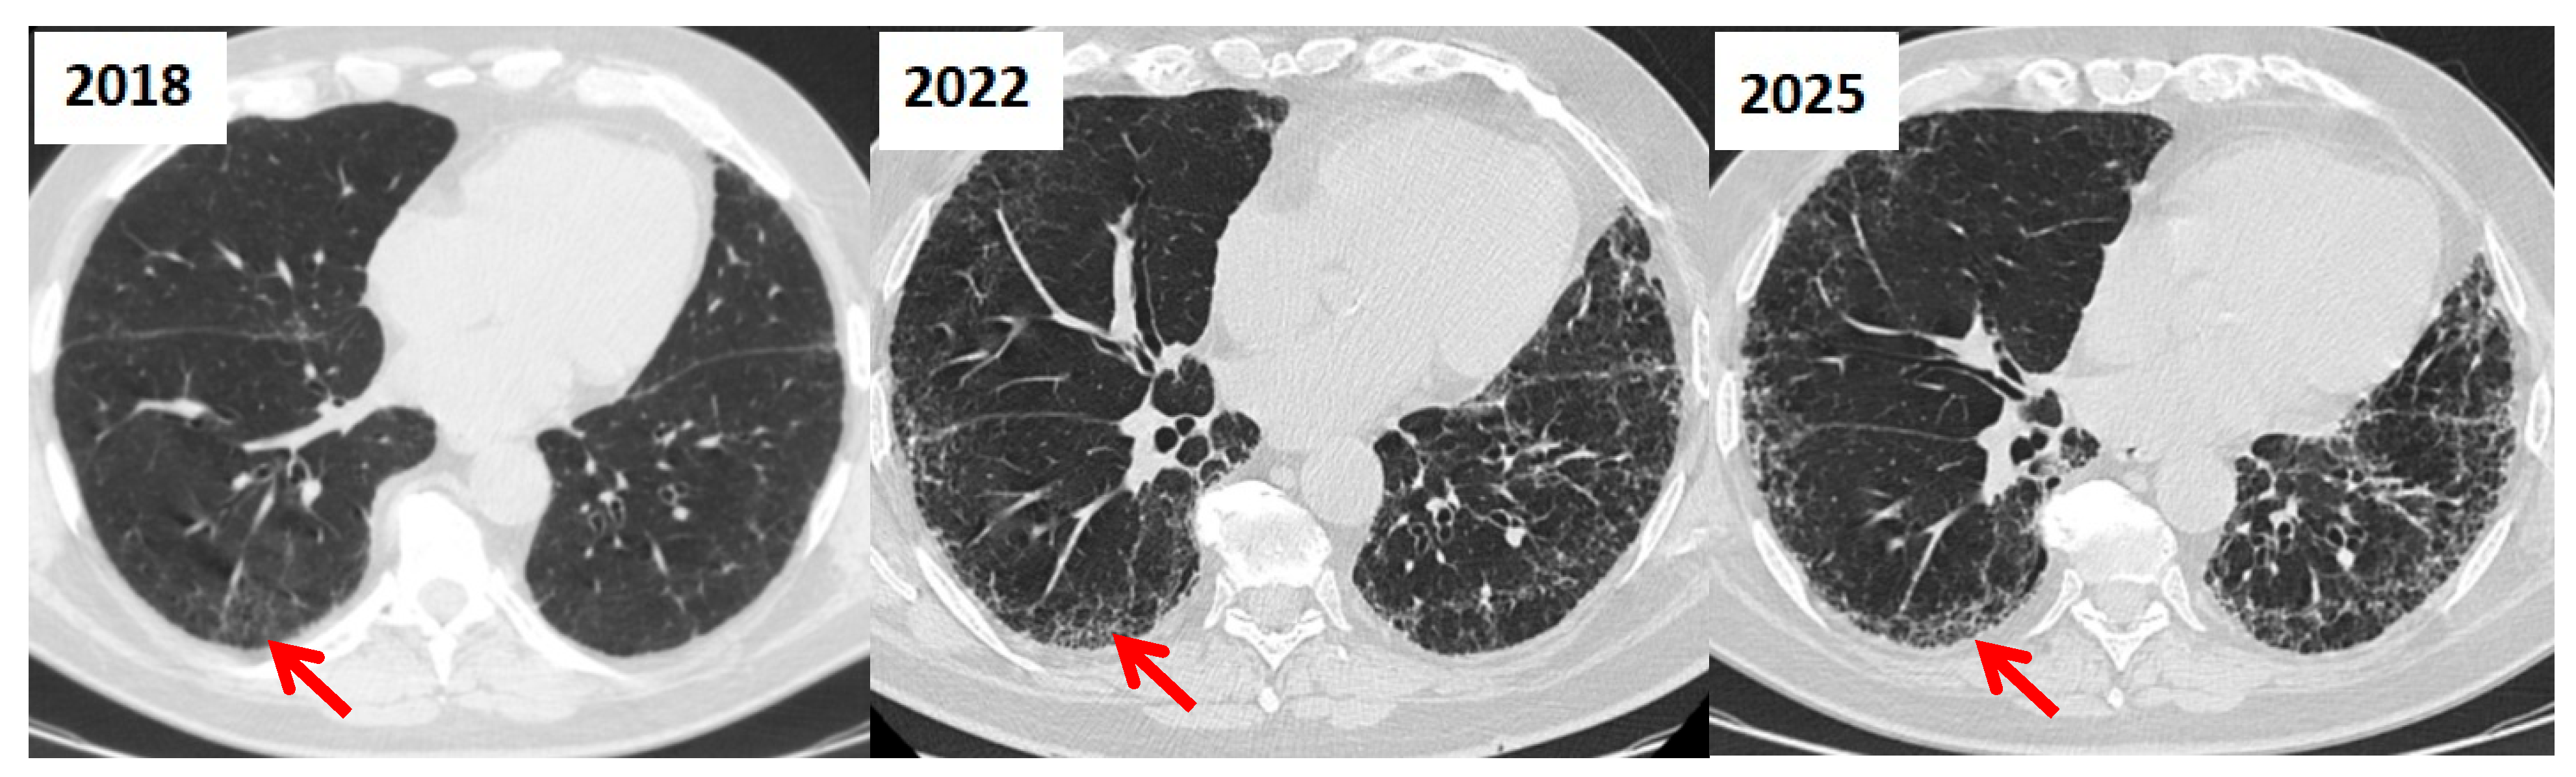

3.5. Role of HRCT in Longitudinal Assessment of CTD-ILD

| HRCT Patterns | - NSIP (~45–75%): ground-glass opacities, lower lobe predominance - UIP (~20–25%): honeycombing, traction bronchiectasis, worse prognosis - OP (~30%) - Other patterns (~5%)  | [32] |

| Esophageal Involvement | - Affects ~90% of SSc patients - Early sign on HRCT: dilated esophageal lumen (1.2–4 cm, mean 2.3 cm) - Can lead to aspiration pneumonia due to dysmotility and reflux  | [10,37] |